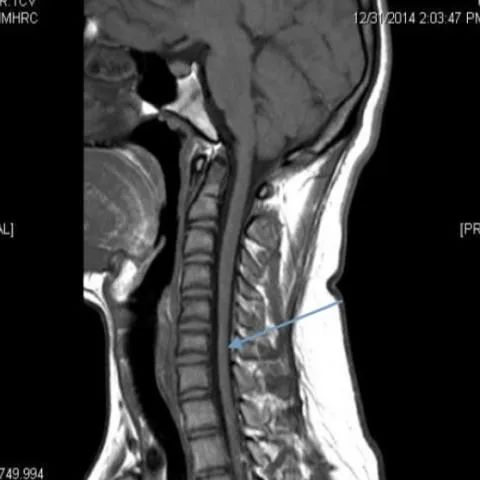

一名19岁男性患者在过去八个月中出现单侧上肢无力。神经学检查显示右前臂和手无力和肌肉萎缩(图1),无感觉障碍。左侧上肢或双侧下肢无感觉或运动障碍。

颈椎核磁共振在这种罕见疾病的诊断中起着重要的作用。矢状位磁共振成像显示细微的局灶性颈髓萎缩(图2 & 3),尤其是在下颈部。屈曲位成像示硬脑膜的前移位,后硬膜外腔增宽(图4)和更明显的脊髓变细,这在中立位不明显(图5)。